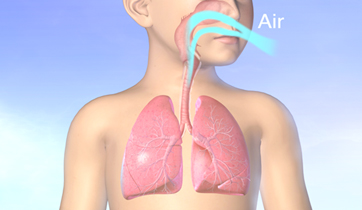

Asthma and its Triggers

Singulair, Merck

Rapp Collins Worldwide

New version in 2012 for UCSF

Patient education animation explaining Asthma and its triggers. The resulting constriction of the airways and the build up of mucus is explained, followed by tactics to maintain airflow and avoid attacks.